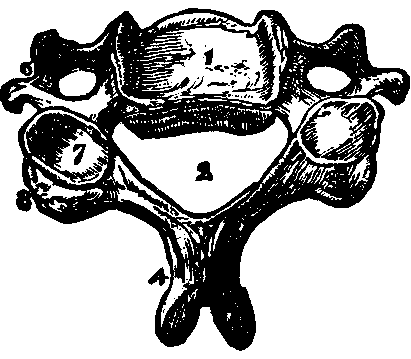

Fig. 12. A vertebra of the

neck. 1. The body of the vertebra. 2. The spinal canal.

4. The spinous process cleft at its extremity. 5. The

transverse process. 7. The interior articular process. 8. The

superior articular process.

The Trunk has fifty-four bones, which are as follows: The Os Hyoides, the Sternum, twenty-four Ribs, twenty-four vertebræ or bones of the Spinal Column, the Sacrum, the Coccyx, and two Ossa Innominata. The Os Hyoides, situated at the base of the tongue, is the most isolated bone of the skeleton, and serves for the attachment of [pg 24]muscles. The Sternum, or breast-bone, in a child is composed of six pieces, in the adult of three, which in old age are consolidated into one bone. The Ribs are thin, curved bones, being convex externally. There are twelve on each side, and all are attached to the spinal column. The seven upper ribs, which are united in front of the sternum, are termed true ribs; the next three, which are not attached to the sternum, but to one another are called false ribs; and the last two, which are joined only to the vertebræ, are designated as floating ribs. The first rib is the shortest, and they increase in length as far as the eighth, after which this order is reversed.

Fig. 13. 1. The

cartilaginous substance which connects the bodies of the vertebræ.

2. The body of the vertebra. 3. The spinous process.

4,4. The transverse processes. 5,5. The articular processes.

6,6. A portion of the bony bridge which assists in forming the

spinal canal (7).

The Spinal Column or backbone, when viewed from the front presents a perpendicular appearance, but a side view shows four distinct curves. The bones composing it are called vertebræ. The body part of a vertebra is light and spongy in texture, having seven projections called processes, four of which are the articular processes, which furnish surfaces to join the different vertebræ of the spinal column. Two are called transverse, and the remaining one is termed the spinous. The transverse [pg 25]and spinous processes serve for the attachment of the muscles belonging to the back. All these processes are more compact than the body of the vertebra, and, when naturally connected, are so arranged as to form a tube which contains the medulla spinalis, or spinal cord. Between the vertebræ is a highly-elastic, cartilaginous and cushion-like substance, which freely admits of motion, and allows the spine to bend as occasion requires. The natural curvatures of the spinal column diminish the shock produced by falling, running or leaping, which would otherwise be more directly transmitted to the brain. The ribs at the sides, the sternum in front, and the twelve dorsal bones of the spinal column behind, bound the thoracic cavity, which contains the lungs, heart, and large blood-vessels.